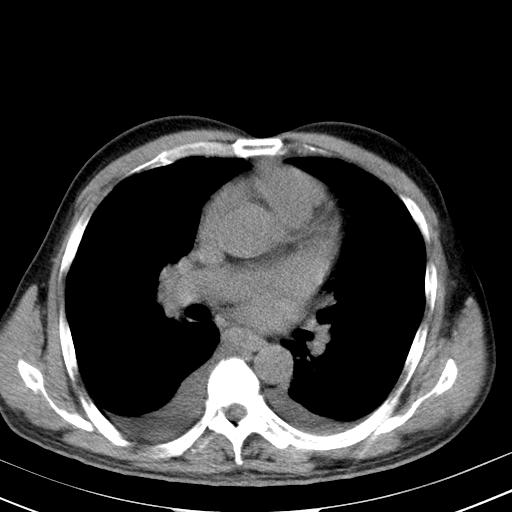

以下是引用zjzjr在2010-3-21 17:39:00的发言:[br]右下中心型肺癌并阻塞性肺炎/不张,纵膈淋巴结肿大,右侧大量胸腔积液,左侧少量胸腔积液

以下是引用zxl51642在2010-3-21 17:06:00的发言:[br]右下中心型肺癌并阻塞性肺炎/不张,纵膈淋巴结肿大,右侧大量胸腔积液,左侧少量胸腔积液,少量腹水。建议纤维支气管镜进一步检查。